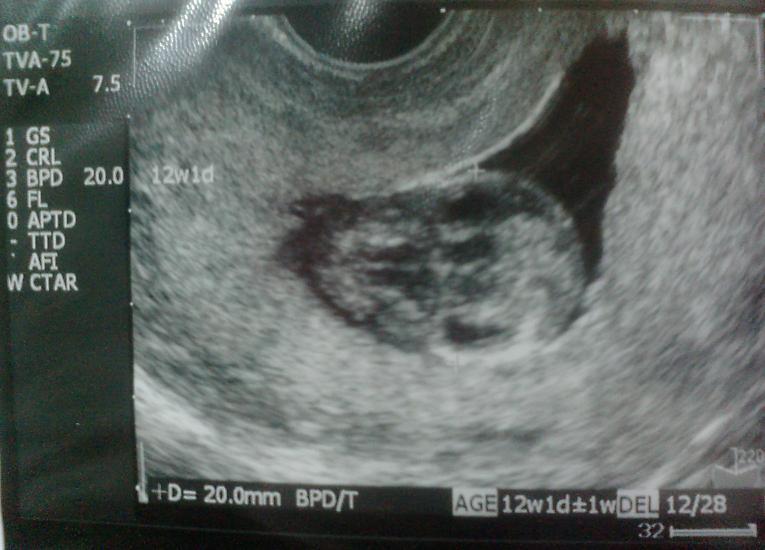

心配していた赤ちゃんもスクスク成長

右が頭で横になっています

超音波してる間、絶え間なくモゴモゴ動いていました

先生も『よく動いてるね』と言うほどで、超音波で計測したくてもじっとしていないので、なかなか大変そうでした

BPDは20.0

数値上では12wとなっていました

成長している証拠だな。。。と安心です♪